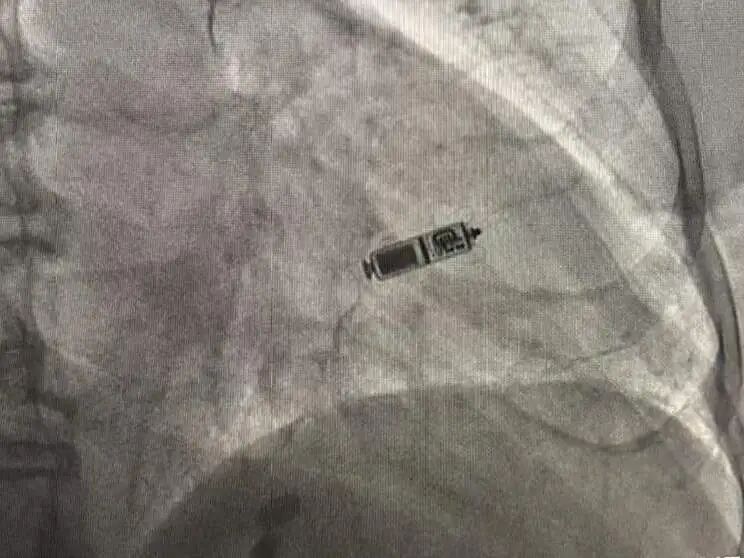

近日,宝山区罗店医院心血管内科主任李岩松带领团队成功为99岁高龄的患者植入Micra无导线胶囊起搏器。这不仅精准地解决了危及患者生命的心脏问题,更让这位近百岁的老人重燃生活“心”希望,同时标志着医院心血管内科在起搏电生理技术领域实现又一重大突破,为更多高龄心动过缓患者带来治疗新曙光。

面对患者家属的重托与期待,心内科团队深感责任重大。在周密分析与评估患者病情后,团队决定为患者植入Micra无导线胶囊起搏器。相较传统起搏器手术中需切开皮肤、制作囊袋并植入电极的操作方式,Micra无导线胶囊起搏器具有创伤极小、术后恢复迅速等显著优势,更能适配高龄患者的身体耐受特点,最大程度降低手术风险。

“参数非常好!”手术中,李岩松团队凭借丰富的临床经验与精湛的操作技术,仅用20分钟就成功为患者精准植入了Micra无导线胶囊起搏器,过程十分顺利。术后,患者恢复良好,心率恢复正常,头晕、心悸症状消失,四肢不自主抖动的情况也得到改善,精神状态和活动能力稳步恢复,重启幸福晚年生活指日可待。

李岩松主任介绍,Micra无导线胶囊起搏器只有维生素胶囊大小,重量仅约2克。手术全程不需要切开胸壁,不需要在皮下制作囊袋,更不需要穿过血管植入长长的电极。这种“无创伤、无导线”的优势,大幅降低了手术创伤与感染风险,尤其适配高龄、体弱或并发症较多的患者,为这类特殊人群的心脏起搏治疗提供了更优选择。